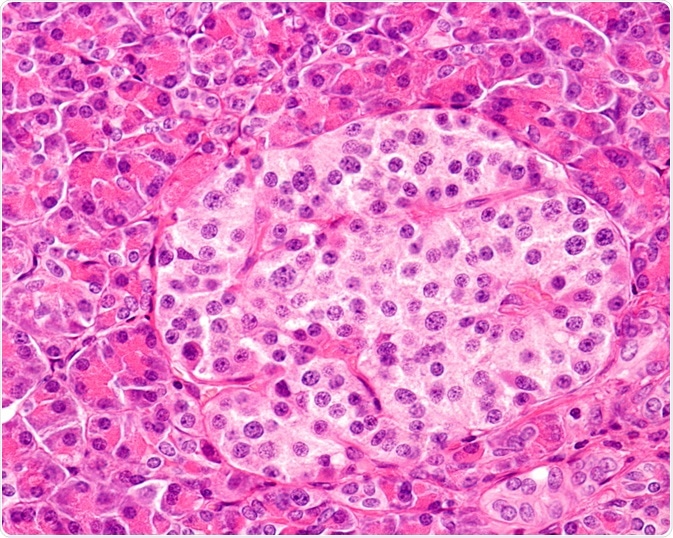

Islet Cells

Image Credit: Jose Luis Calvo/Shutterstock.com